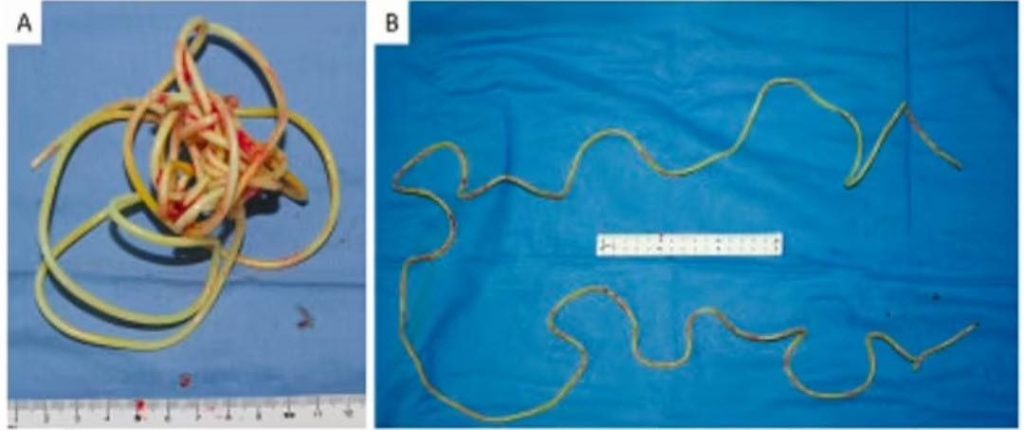

Les scans publiés par ses médecins montrent la corde étroitement enroulée à l’intérieur de la vessie de l’homme non identifié. Les médecins ont dû couper la vessie de l’homme pour l’extraire chirurgicalement et ils n’ont pas pu la retirer comme elle est entrée.

Les médecins ont utilisé des informations provenant d’analyses détaillées pour créer un modèle informatique 3D de la corde emmêlée afin de déterminer la meilleure méthode de retrait. L’homme n’a pas dit aux médecins pourquoi il avait inséré la corde.

L’auteur principal du rapport de cas, publié dans la revue Urology Case Reports, l’urologue professeur Toshiki Kijima, a déclaré que les médecins avaient ensuite effectué un scanner pour déterminer la meilleure façon de retirer la corde. Il a dit qu’ils avaient ensuite utilisé un programme informatique pour générer une reconstruction 3D de la corde qui montrait qu’elle était devenue trop enchevêtrée pour la retirer à travers le p3nis. La corde s’est emmêlée lorsque la vessie s’est contractée, un processus naturel qui se produit après l’expulsion de l’urine stockée. « L’extraction transurétrale était difficile compte tenu de la longueur de la corde et de son enchevêtrement dans la vessie », a déclaré le professeur Kijima.

Cela a forcé les médecins à retirer chirurgicalement la corde directement à travers une petite incision coupant l’abdomen de l’homme, puis à la retirer de la vessie dans son intégralité. Ils ont dit qu’en la retirant de cette façon, ils évitaient d’endommager potentiellement son urètre ou sa vessie en tirant avec force le cordon emmêlé hors de son p3nis.